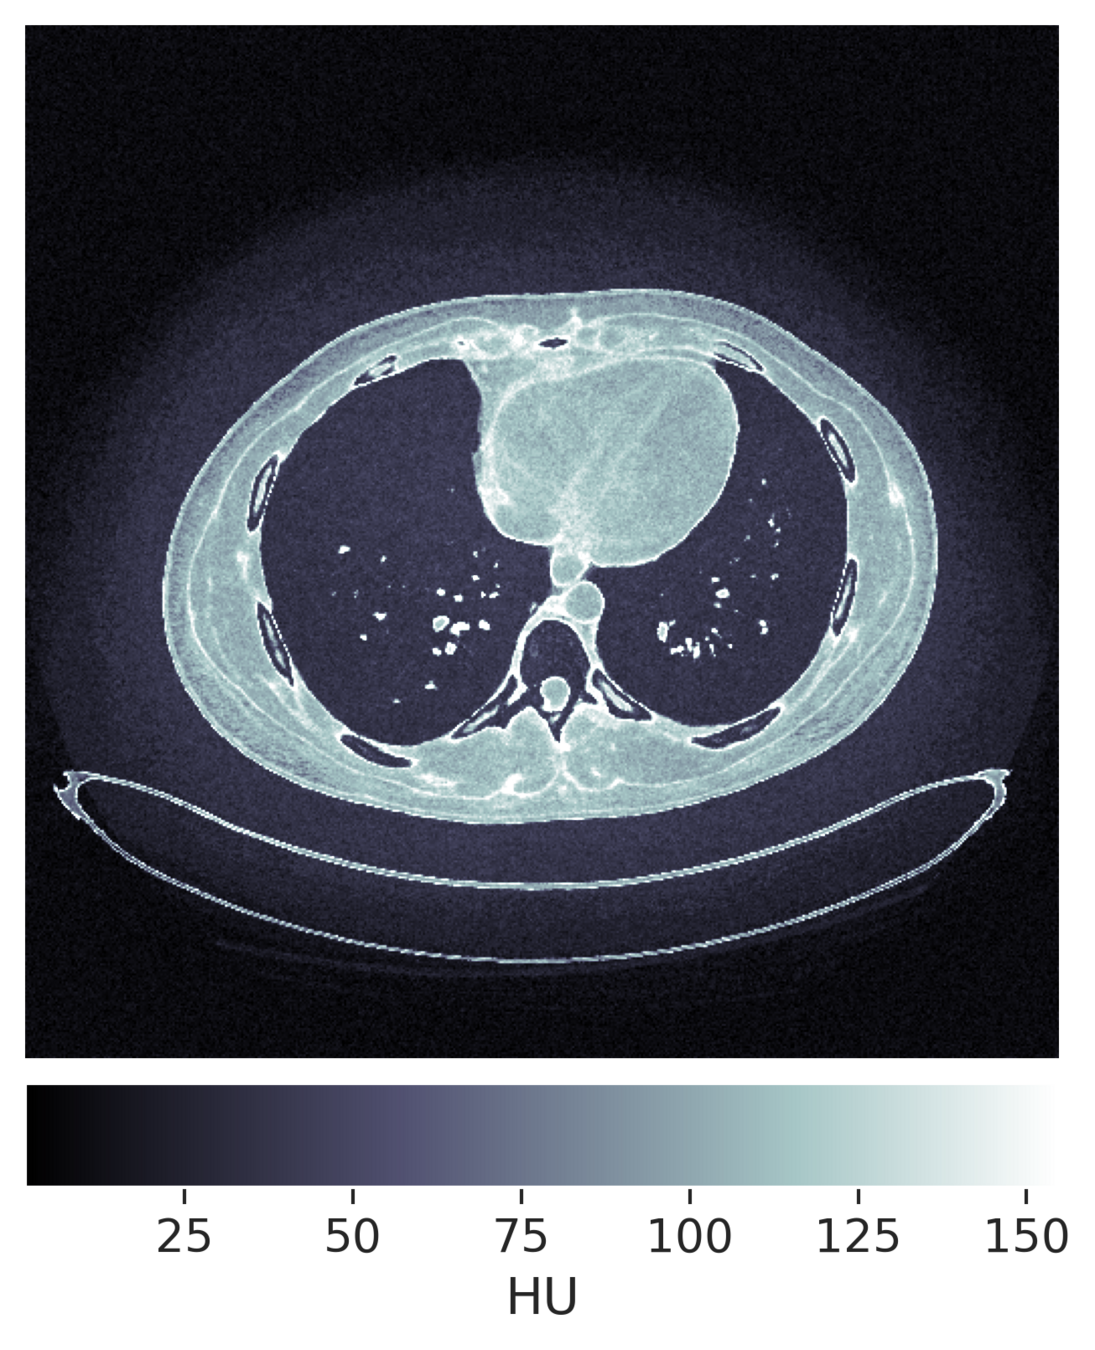

Uncertainty Quantification

How to quantify and report uncertainty?

Filtered Back Projection

Diffusion Model

For an observation \(y\)

\[y = x + \epsilon,~\epsilon \sim \mathcal{N}(0, \sigma^2\mathbb{I})\]

reconstruct \(x\) with

\[\hat{x} = F(y) \sim \mathcal{Q}_y \approx p(x \mid y)\]

\(K\)-RCPS: High-dimensional Risk Control

scalar \(\lambda \in \mathbb{R}\)

\(\mathcal{I}_{\lambda}(y)_j = [\text{low} - \lambda, \text{up} + \lambda]\)

\(\rightarrow\)

vector \(\bm{\lambda} \in \mathbb{R}^d\)

\(\mathcal{I}_{\bm{\lambda}}(y)_j = [\text{low} - \lambda_j, \text{up} + \lambda_j]\)

Guarantee:    \(\mathcal{I}_{\bm{\lambda}}(y)_j = [\text{low} - \lambda_j, \text{up} + \lambda_j]\)   are RCPS

For a \(K\)-partition of the pixels \(M \in \{0, 1\}^{d \times K}\)

\(K=4\)

\(K=8\)

\(K=32\)

\(\hat{\lambda}_K\)

conformalized uncertainty maps

Teneggi, J., Tivnan, M., Stayman, W., & Sulam, J. (2023, July). How to trust your diffusion model: A convex optimization approach to conformal risk control. In International Conference on Machine Learning. PMLR.